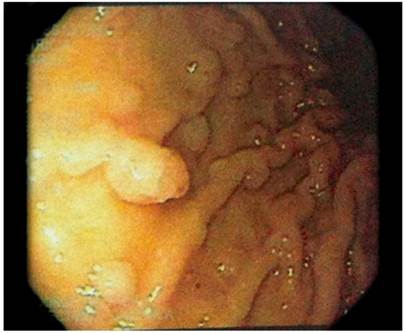

A gastroduodenoscopy showed white cottony points in the second portion of the duodenum with multiple sessile polypoid lesions in the corpus and fundus (Figure 4).

Hyperplastic oxyntic gland adenoma with dilation of glandular crypts and chronic mucosal inflammation in the gastric corpus.

Figure 4 Gastroduodenoscopy. (A) Fundus (B) Corpus with multiple sessile polyps of various diameters.